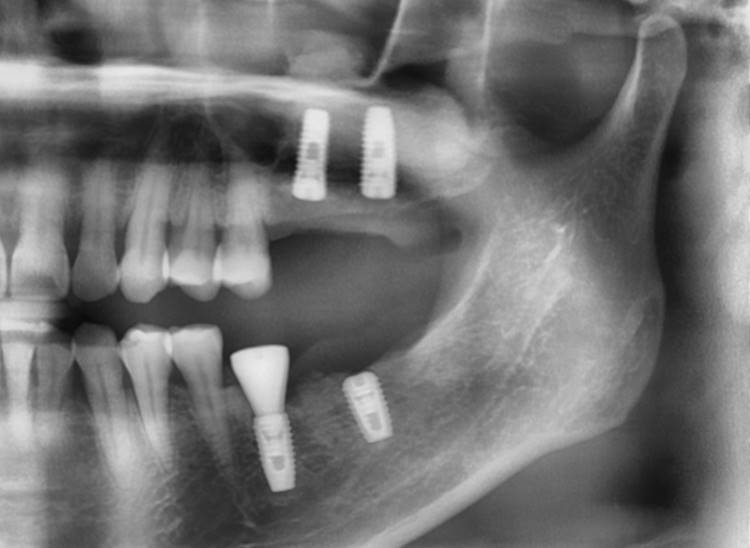

▲post-op panoramic radiograph.

▲. Panoramic radiograph after implant placement in the maxilla.(3 weeks after implant placement in the mandible)